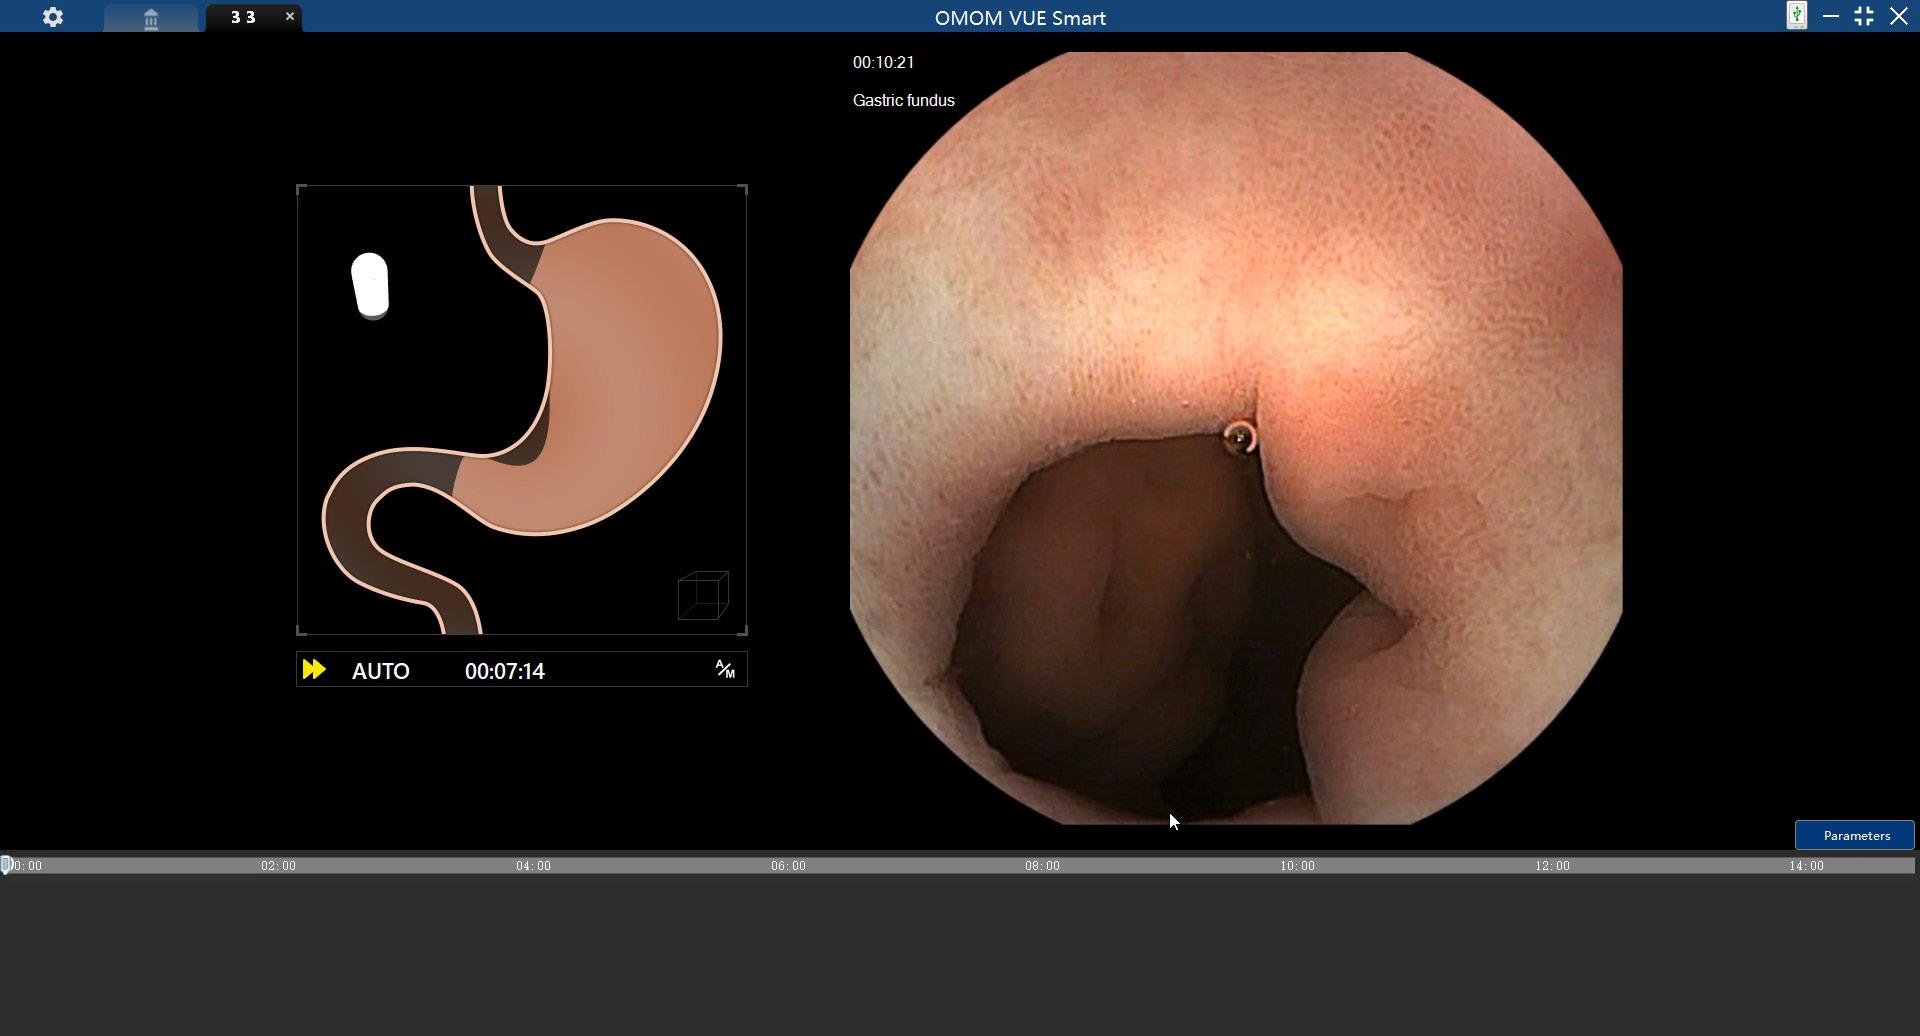

The Control Console serves as the control center. When connected with the Robotic Movement Unit, healthcare professionals can start the gastric examination automatically by simply pressing the AUTO button on the Control Console after the patient is ready. Manual mode is also available in case doctors want to control the capsule manually. The Control Console is installed with VUE Smart software for reporting.

Fully Automated, OMOM RC has revolutionized capsule movement control. Proprietary algorithms have been developed to detect the anatomical gastric landmarks. Those algorithms have been pre-programmed into the control system to automatically guide the Robotic Movement Unit to navigate the capsule. The capsule is moved in translational and rotational direction to capture the gastric images until the full gastric coverage is achieved when the Robotic Movement Unit stops automatically.

All six gastric anatomical landmarks, cardia, fundus, body, angulus, antrum and pylorus, are covered. It takes about 12 minutes to complete the gastric examination.

VUE Smart Assisted Diagnosis

During a gastric examination, eight types of focal lesions (gastritis, polyps, tumors, ulcers, erosions, xanthomas, telangiectasia and diverticulum) can be detected and tagged with real-time display. In addition, intelligent abnormality detection assists in quick and accurate diagnosis.